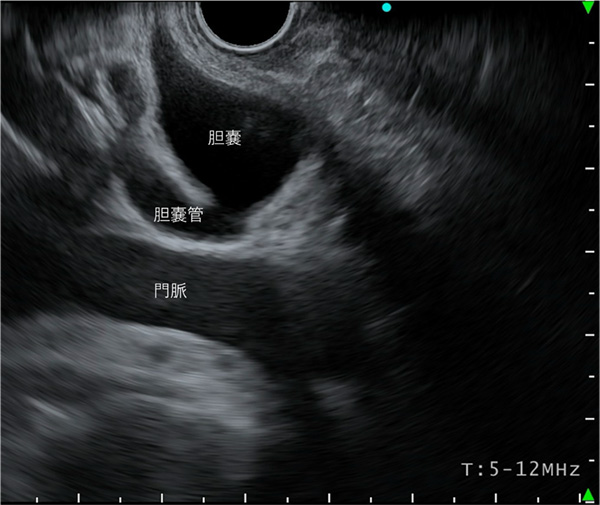

肝門部からVater乳頭まで観察します。特にこの領域は、胆管の観察に充填をおきます。

〈十二指腸球部操作による観察〉

胆管を肝門方向に観察していくと、胆嚢管及び胆嚢の描出が可能となります。